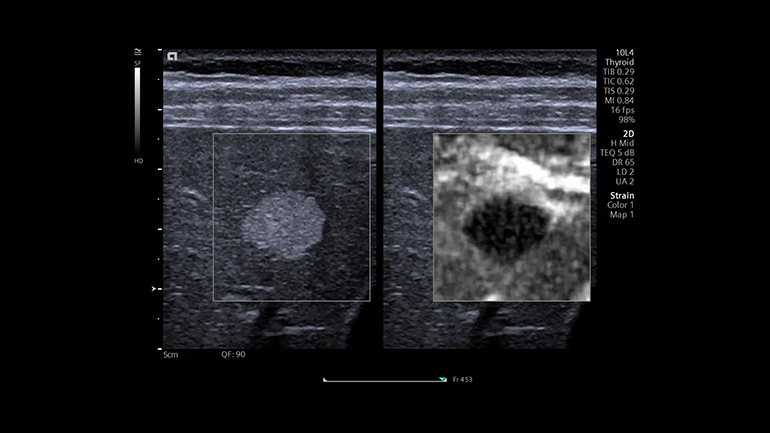

Технология для определения скорости распространения поперечной волны при работе с линейными и конвексными датчиками. Двумерная эластография со сдвиговой волной (SWE). Это технология качественной и количественной диагностики, с помощью которой можно получить цветовые карты жесткости тканей молочной и щитовидной желез, используя для этого датчик 10L4, а также конкретные цифровые значения скорости распространения поперечной волны. Технология визуализации эластичности ткани с использованием мануальной компрессии для линейных датчиков. Метод мануальной деформационной эластографии Virtual Touch обеспечивает простое и качественное измерение жесткости пораженного участка относительно окружающих неповрежденных тканей.

Технология визуализации эластичности ткани с использованием мануальной компрессии для линейных датчиков. Метод мануальной деформационной эластографии Virtual Touch обеспечивает простое и качественное измерение жесткости пораженного участка относительно окружающих неповрежденных тканей. УЗИ с контрастным усилением (CEUS) с помощью визуализации с контрастным веществом. Технология импульсных последовательностей контрастного усиления эхо-сигнала от микропузырьков контрастного препарата (CPS) и технология коротких импульсов с большим механическим индексом позволяют более уверенно диагностировать очаги поражения печени.